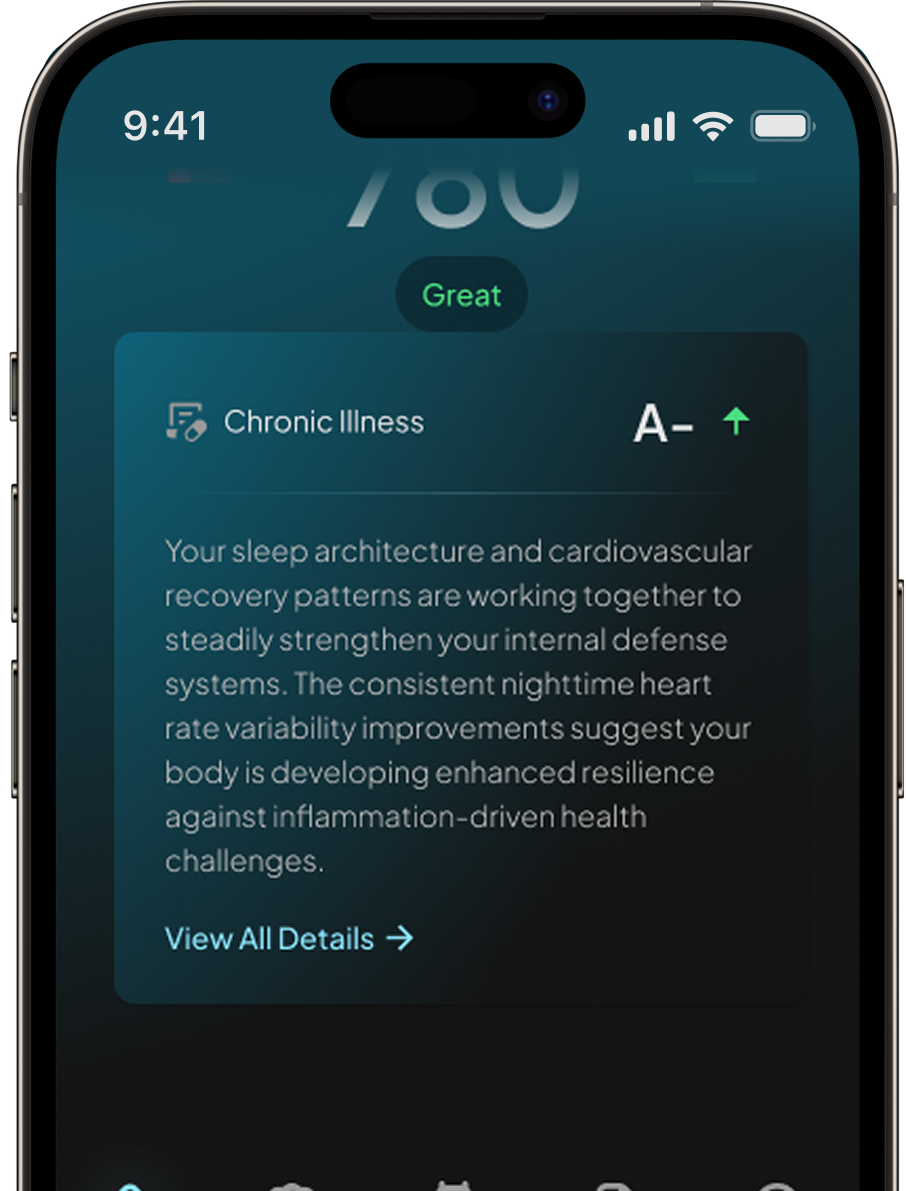

Chronic illness detection

May indicate the

onset of an illness

Identify potential health issues early and take action before they become serious.

By analyzing your body’s signals, Hume Band may detect early signs of illness—helping you take action before small issues become big problems

By analyzing your body’s signals, Hume Band may detect early signs of illness—helping you take action before small issues become big problems

We constantly scan your biometrics to detect early signs of stress, immune decline, inflammation, and recovery delays—so you can act before illness takes hold.